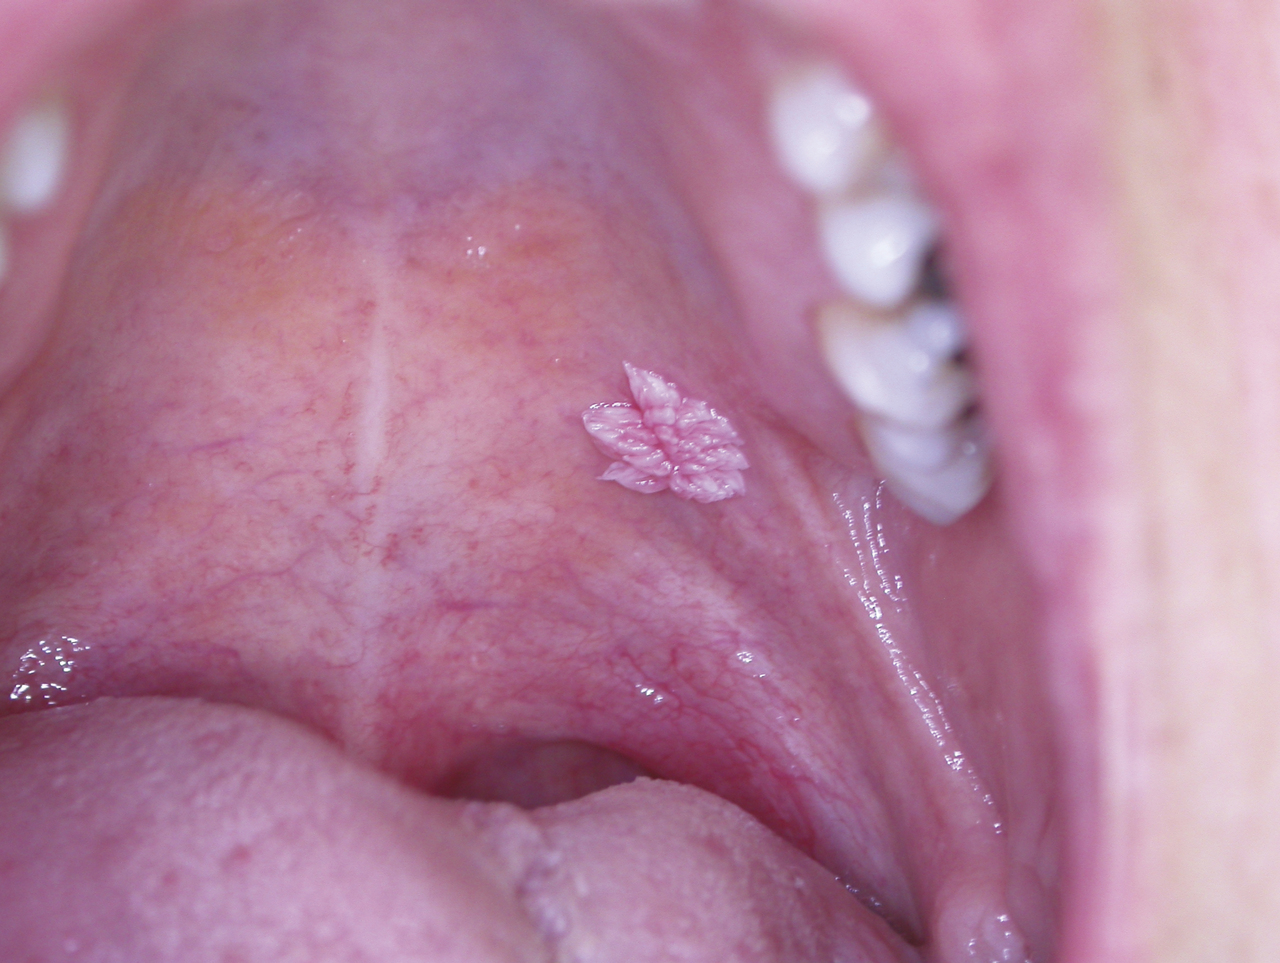

Les papillomavirus humains qui ont un tropisme pour les kératinocytes des épithéliums malpighiens sont responsables de tumeurs bénignes (verrues, papillomes, condylomes) ; certains d’entre eux sont oncogènes (col de l’utérus, carcinomes épidermoïdes pharyngolaryngés) ; leur implication dans la survenue de carcinomes épidermoïdes de la cavité buccale n’est pas démontrée. Les papillomes sont des élevures de quelques millimètres de diamètre, indolores à surface kératosique (fig. 7 ), des verrues digitales sont parfois à l’origine de l’auto-inoculation. Les condylomes acuminés sont rares sur la muqueuse buccale, leur transmission est sexuelle. L’évolution spontanée est variable, ils persistent ou se multiplient mais peuvent également régresser spontanément. La présence de papillomes multiples (fig. 8 ) fait rechercher une immunodépression. Le traitement repose sur la destruction des lésions (chirurgie, laser CO2) ; les récidives sont possibles.

Les papillomavirus humains qui ont un tropisme pour les kératinocytes des épithéliums malpighiens sont responsables de tumeurs bénignes (verrues, papillomes, condylomes) ; certains d’entre eux sont oncogènes (col de l’utérus, carcinomes épidermoïdes pharyngolaryngés) ; leur implication dans la survenue de carcinomes épidermoïdes de la cavité buccale n’est pas démontrée. Les papillomes sont des élevures de quelques millimètres de diamètre, indolores à surface kératosique (